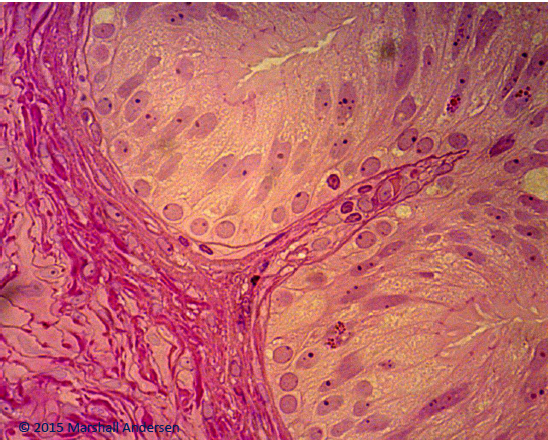

Identify the tissue type and location

Stratified squamous (lightly keratonized)